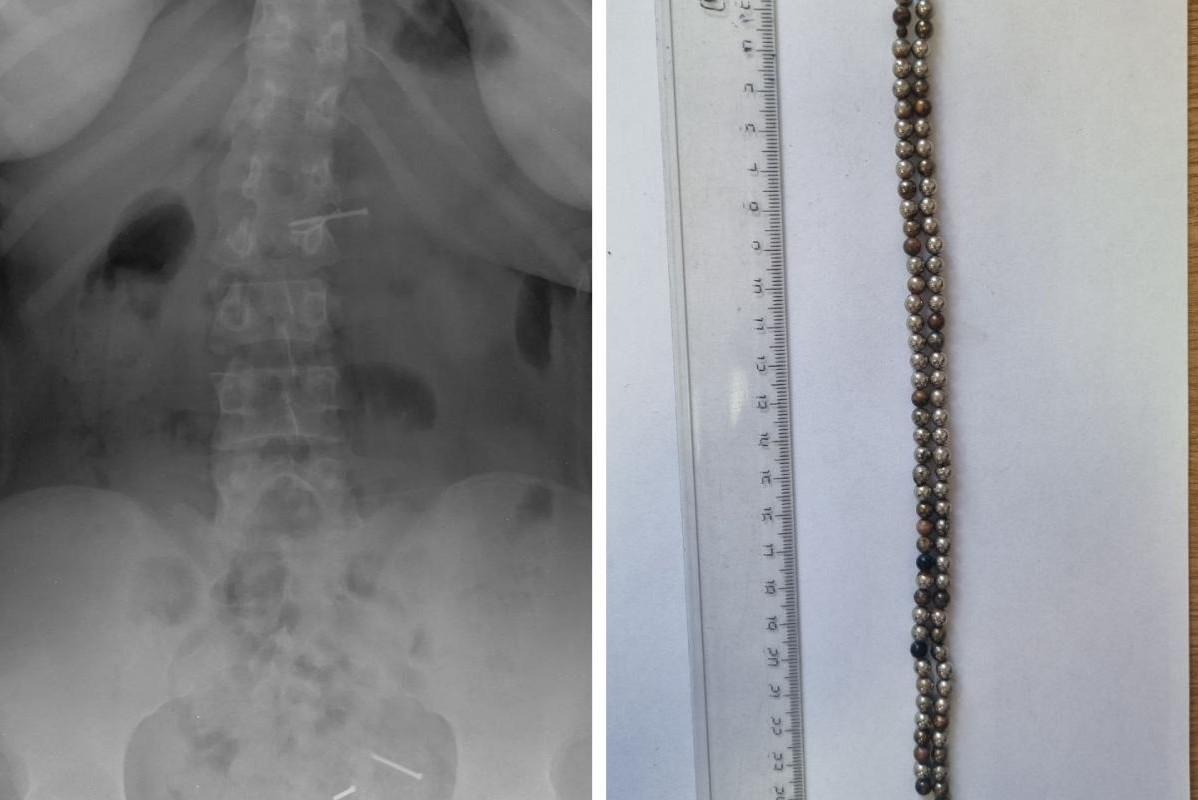

«Провели экстренную операцию»: в Новосибирске ребенок проглотил 25 магнитовСколько лет ребенку — не уточняется

12 декабря, 2025, 17:05

11 126